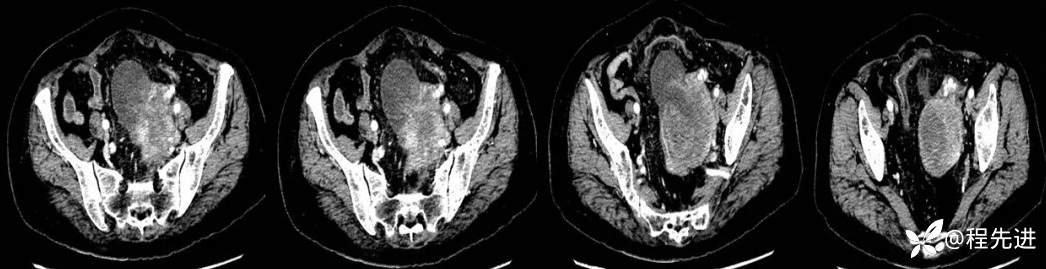

4月后患者再次腹痛半月来诊

CT平扫+增强: